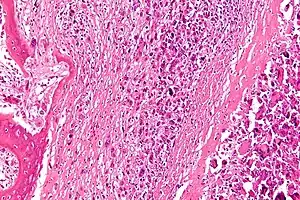

| Micrograph of an osteosarcoma, a malignant primary bone tumor. | |